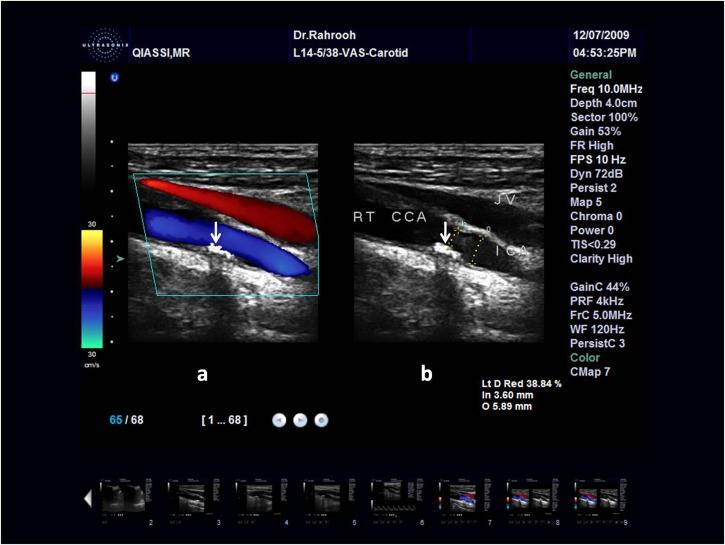

A total of 960 panoramic radiographs of patients above 40 years old were evaluated. Doppler Sonography (DS) was performed for patients who showed calcified carotid artery atheroma (CCAA) in panoramic radiogra-phy in order to determine the presence of CCAA and the degree of stenosis. Cardiovascular risk factors in both groups of patients with CCAA (12 subjects) and without CCAA (3 subjects) were compared using a questionnaire filled out by the patients. Statistical analysis including Fisher and independent t-test applied for data analysis.

Fifteen patients (30 sides) showed calcification in their panoramic radiographs, and underwent DS which revealed CCAA in 16 sides (12 patients). Two patients (13.33%) showed stenosis greater than 70%. Among the risk factors, only age showed a significant association with the occurrence of carotid calcified atheroma (P=0.026).